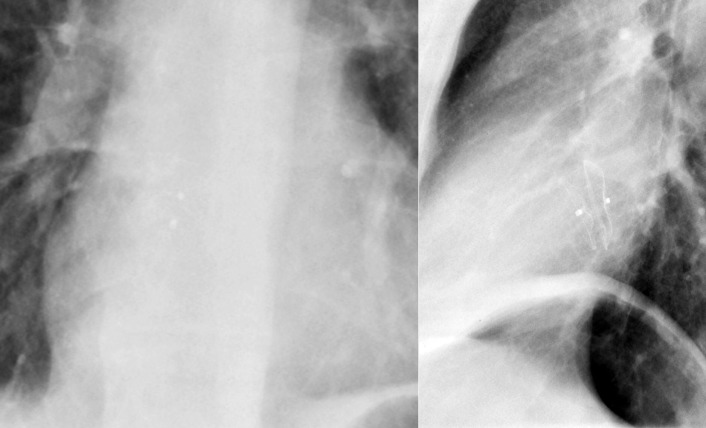

Left-to-right shunts initially result in volume overload of the chambers carrying the shunt volume, causing enlargement of the volume-overloaded chambers and an increase in pulmonary blood flow. If the amount of pulmonary blood flow is sufficiently high, obliterative disease of the pulmonary arterioles develops (“pulmonary vascular disease”), resulting in pulmonary hypertension. The chest radiographic appearance of pulmonary hypertension is one of centralization of pulmonary flow and accelerating enlargement of the right-sided chambers.

The chest radiograph is predominantly useful to detect/characterize the pulmonary vascularity as influenced by congenital shunt lesions, such as pulmonary vascular shunt plethora of larger shunts and signs of pulmonary hypertension complicating large shunts.